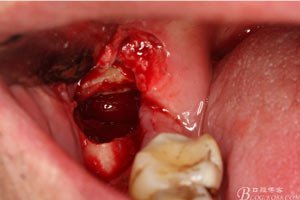

圖7.高速牙鉆去骨。逐漸可見(jiàn)48的牙冠

圖8.刮除牙冠表面的肉芽組織后,可見(jiàn)48 的牙冠